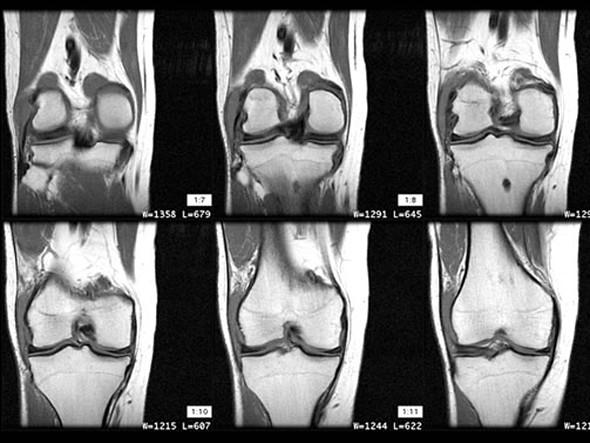

请根据所提供的图像,选择最佳选项是 ( )A、半月板损伤B、半月板囊变C、桶状半月板D、半月板黏液样变E、盘状半月板

问题 请根据所提供的图像,选择最佳选项是 ( )

选项 A、半月板损伤 B、半月板囊变 C、桶状半月板 D、半月板黏液样变 E、盘状半月板

答案 E